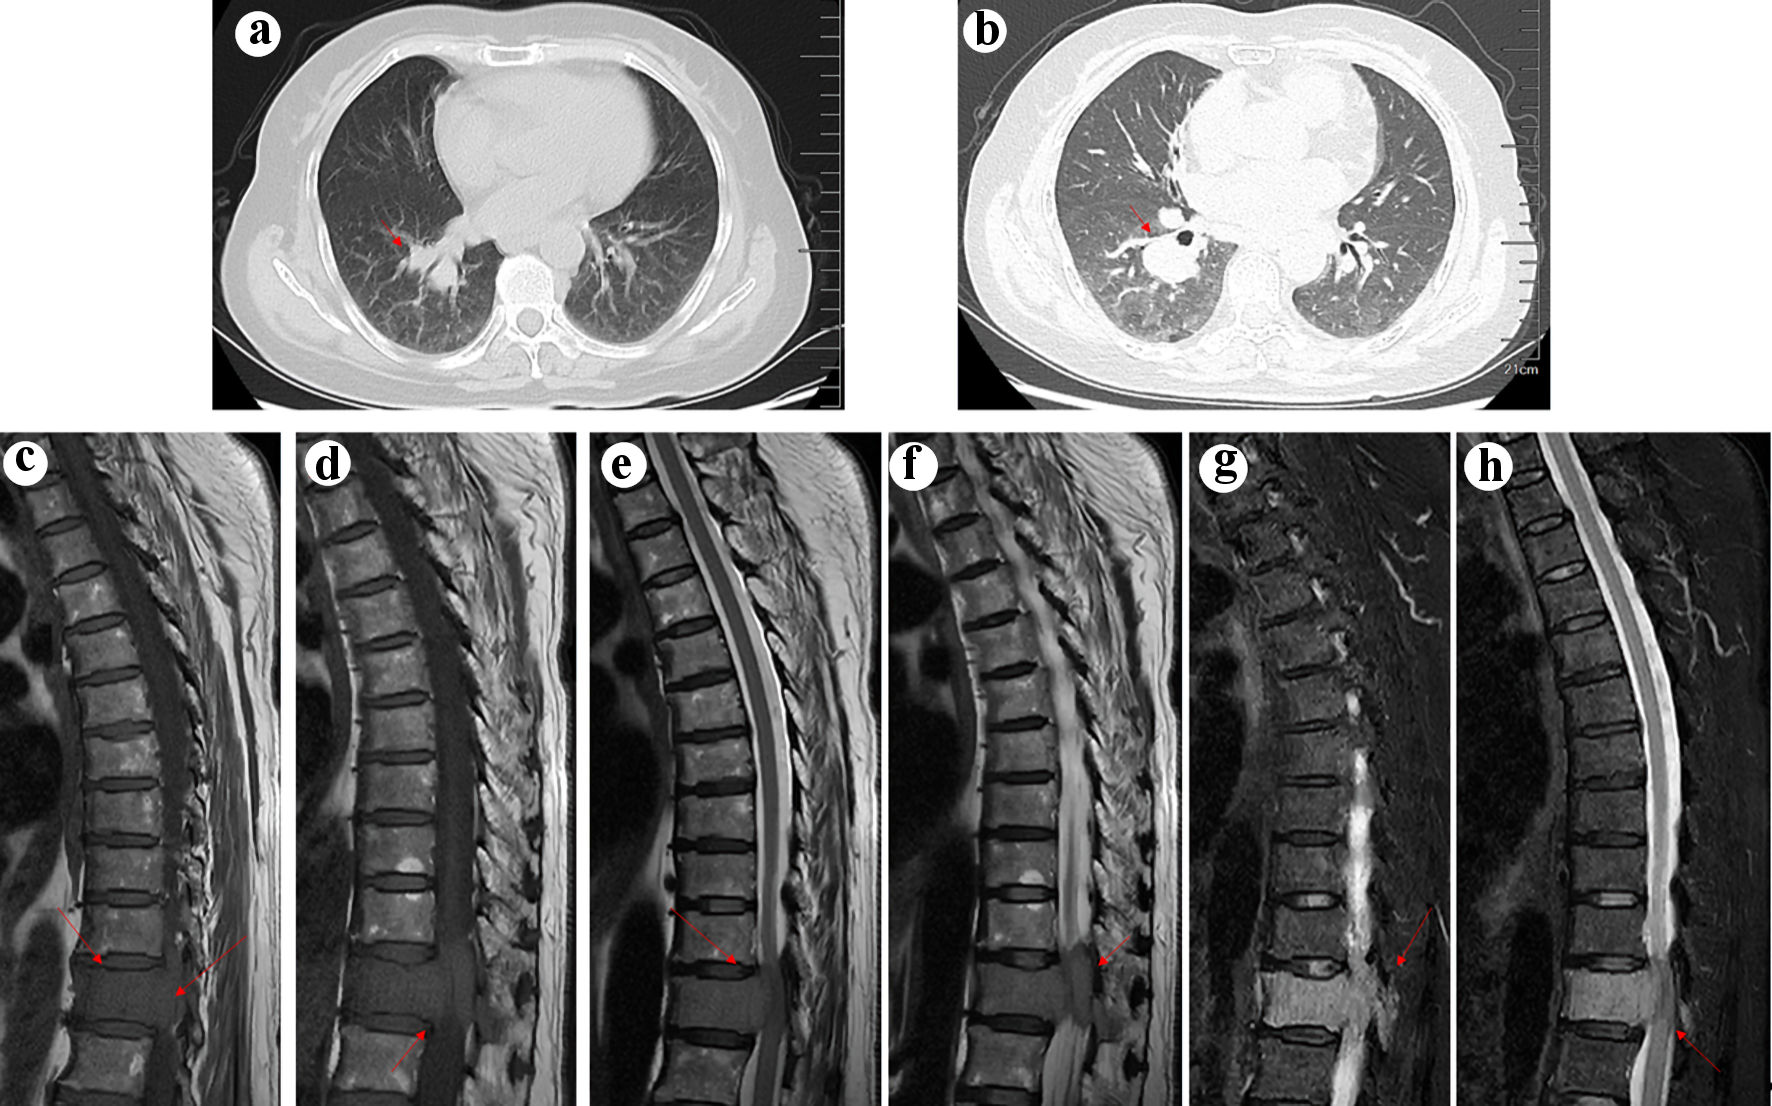

Pulmonary nodules with enlarged hilar and mediastinal lymph nodes were found in the right lung on chest computed tomography (CT) (Fig. 1). Subsequent magnetic resonance imaging (MRI) of the spine revealed a homogeneous mass lesion arising from the T11 vertebral body. The lesion involved the vertebral body and its appendix of T11 with extension into the thoracic canal and compression of the spinal cord, which highly supported the diagnosis of metastatic malignancy (Fig. 1). The patient was preliminarily diagnosed with metastatic epidural spinal cord compression from LC based on the results of imaging and laboratory examination. Considering that radical resection of metastatic tumors may not affect overall survival, we planned to treat the patient with direct surgical resection and decompression followed by spinal stabilization to improve her quality of life [5]. However, pathologic examination revealed that the tissue obtained from the spine during the operation was CD38- and CD138-positive, whereas kappa and lambda were negative, supporting the diagnosis of MM (Fig. 2). Finally, the diagnosis of LC and MM derived from the spine were determined. As for LC, we consulted a respiratory physician who staged them as T2N2M0 stage III-A. However, the lung lesion was undetermined by biopsy.

![]() Click for large image | Figure 1. (a) Computed tomography (CT) scan showing a neoplasm in the right lung (arrow). (b) Enhanced CT scan confirmed the existence of neoplasm in the right lung (arrow). Arrows indicate the location of the tumor. T1 (c and d), T2 (e and f), and fat-suppressed T2WI weighted spin echo magnetic resonance image of the thoracic spine in the sagittal planes (g, h). The tumor (arrow) showed hyperintensity on T1WI, mild hypointensity on T2WI, and hyperintensity on fat-suppressed T2WI, mimicking metastatic lung cancer. |